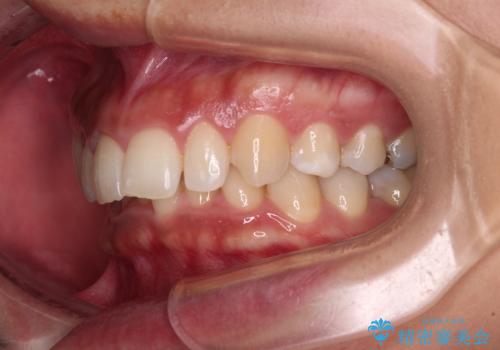

抜歯矯正で口が閉じやすく|ディープバイトと叢生を改善した症例

- 下顎前歯部には叢生が認められ、口を自然に閉じにくい状態でした。また、噛み合わせが深い「ディープバイト」の状態で、見た目だけでなく将来的な奥歯への負担も懸念されました。

口元の突出感を改善するため、上下左右の小臼歯4本を抜歯する矯正治療を計画しました。

抜歯矯正は「歯を抜くのが不安」と感じられる方も多いですが、

適切な診断と治療計画により、口元・噛み合わせ・将来的な安定性を同時に改善することが可能です。